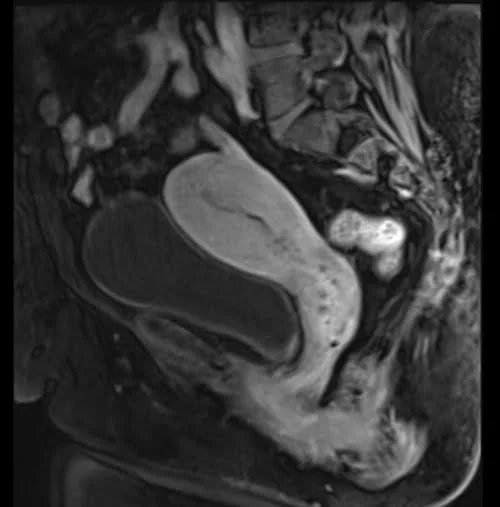

VIBE FAT SAT SAGITTAL POST CONTRAST SEQUENCE USED IN GYNECOLOGICAL PELVIS IMAGING

Uterus:- bright

Prostate :- bright

The easiest way to identify T1 VIBE fat-saturated post-gadolinium images is to look for adipose tissues (e.g., subcutaneous fat and fat in bone marrow) and blood vessels in the body (e.g., arteries and veins in the chest, abdomen, upper limbs, and lower limbs). Areas containing adipose tissues appear dark on T1 VIBE fat-saturated post-gadolinium images. Blood vessels and pathologies with high vascularity appear bright on T1 VIBE fat-saturated post-gadolinium images. All other characteristics of the T1 VIBE fat-saturated post-gadolinium images remain the same as the T1 VIBE images.

Pathologies with adipose tissue content will appear dark on T1 VIBE fat-saturated post-gadolinium images (e.g., lipoma). Pathologies with hypervascularization will appear bright on T1 VIBE fat-saturated post-gadolinium images (e.g., tumors like hemangioma, lymphangioma, hemangioendothelioma, Kaposi sarcoma, angiosarcoma, hemangioblastoma, etc., and inflammatory processes like discitis, meningitis, synovitis, arthritis, osteomyelitis, etc.). Pathological processes with no vascularity will remain unenhanced (appearing dark on T1 VIBE fat-saturated post-gadolinium images).